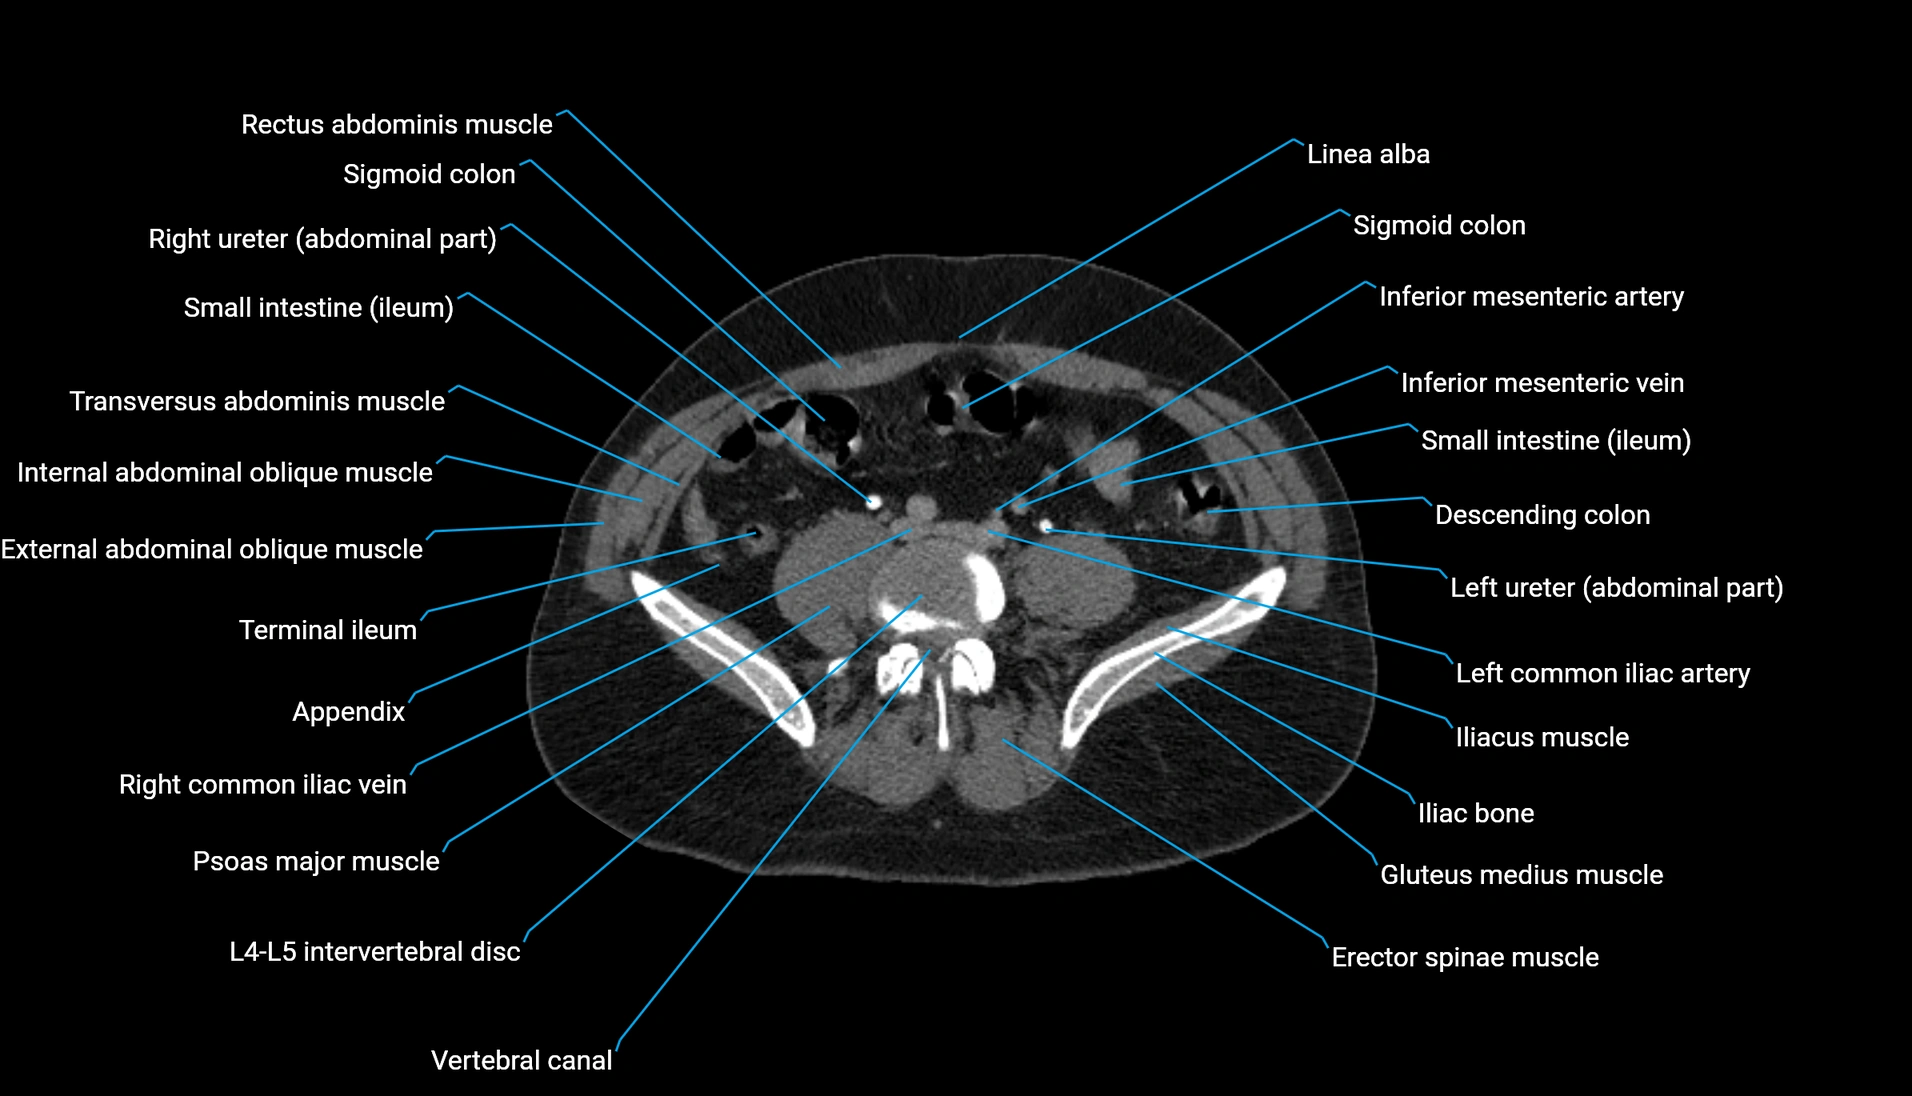

CT Appearance

Non-contrast CT:

-

Demonstrates cortical bone of acetabular rim in excellent detail

Detects fractures, dysplasia, retroversion, or bony overcoverage (pincer impingement)

3D reconstructions used in preoperative hip surgery planning

CT VRT 3D image

CT image